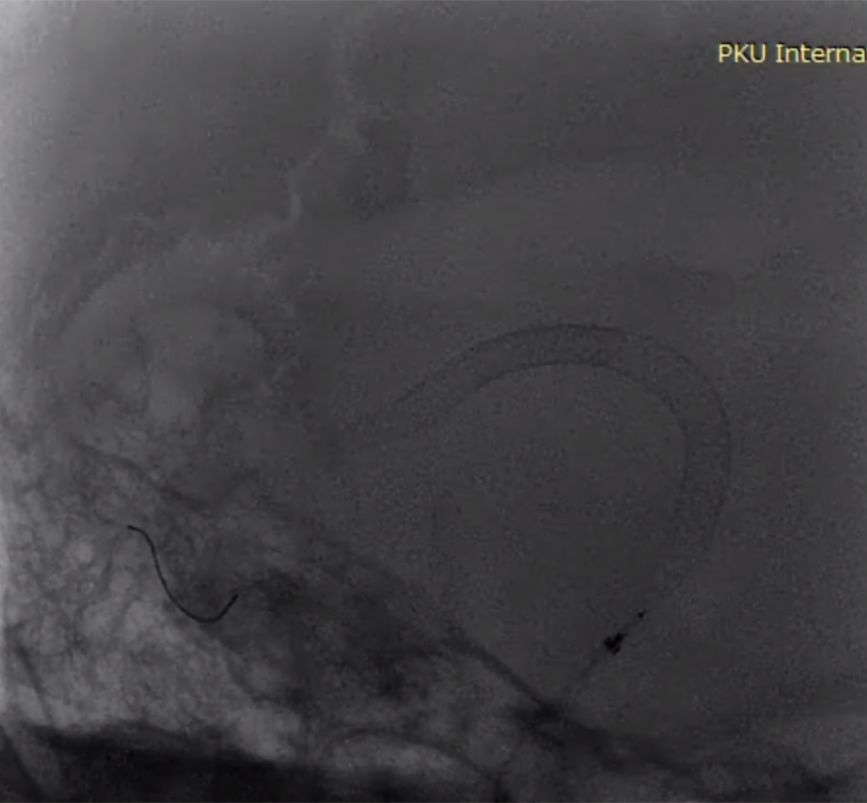

(3)第三枚PED 5mm×35mm桥接,可见近端已着陆于相对正常血管,但支架长度明显长于35mm,且近端血管转折处仍可见瘤样改变(图6)。

滑动查看更多

图6

(4)第四枚PED 5mm×35mm桥接第三枚支架,开始释放时贴壁不良,继续推出一段后支架展开,海绵窦垂直段支架展开形态欠佳,回收后推送形态不变,考虑存在狭窄(图7)。

图7

(5)支架导引导丝按摩支架,形态无变化,较稳定。XperCT提示该出血管转折较明显,支架贴壁欠佳(图8)。

图8

(6)造影见动脉瘤内血流通路形成(图9)。

图9